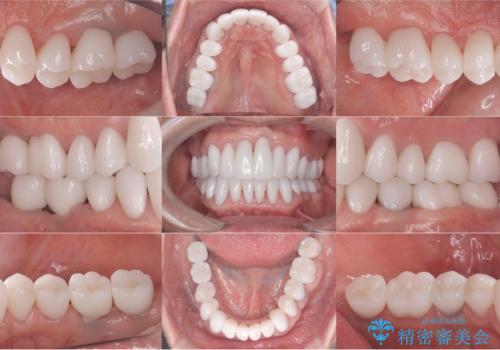

[メタルフリー] 虫歯・銀歯だらけの口腔内を全顎治療

![[メタルフリー] 虫歯・銀歯だらけの口腔内を全顎治療の症例 治療後](https://seimitsushinbi.jp/wp/wp-content/uploads/2025/03/530cf6cca6451bc106a9fb69dd58908a-500x350.jpg?v=1741918343)